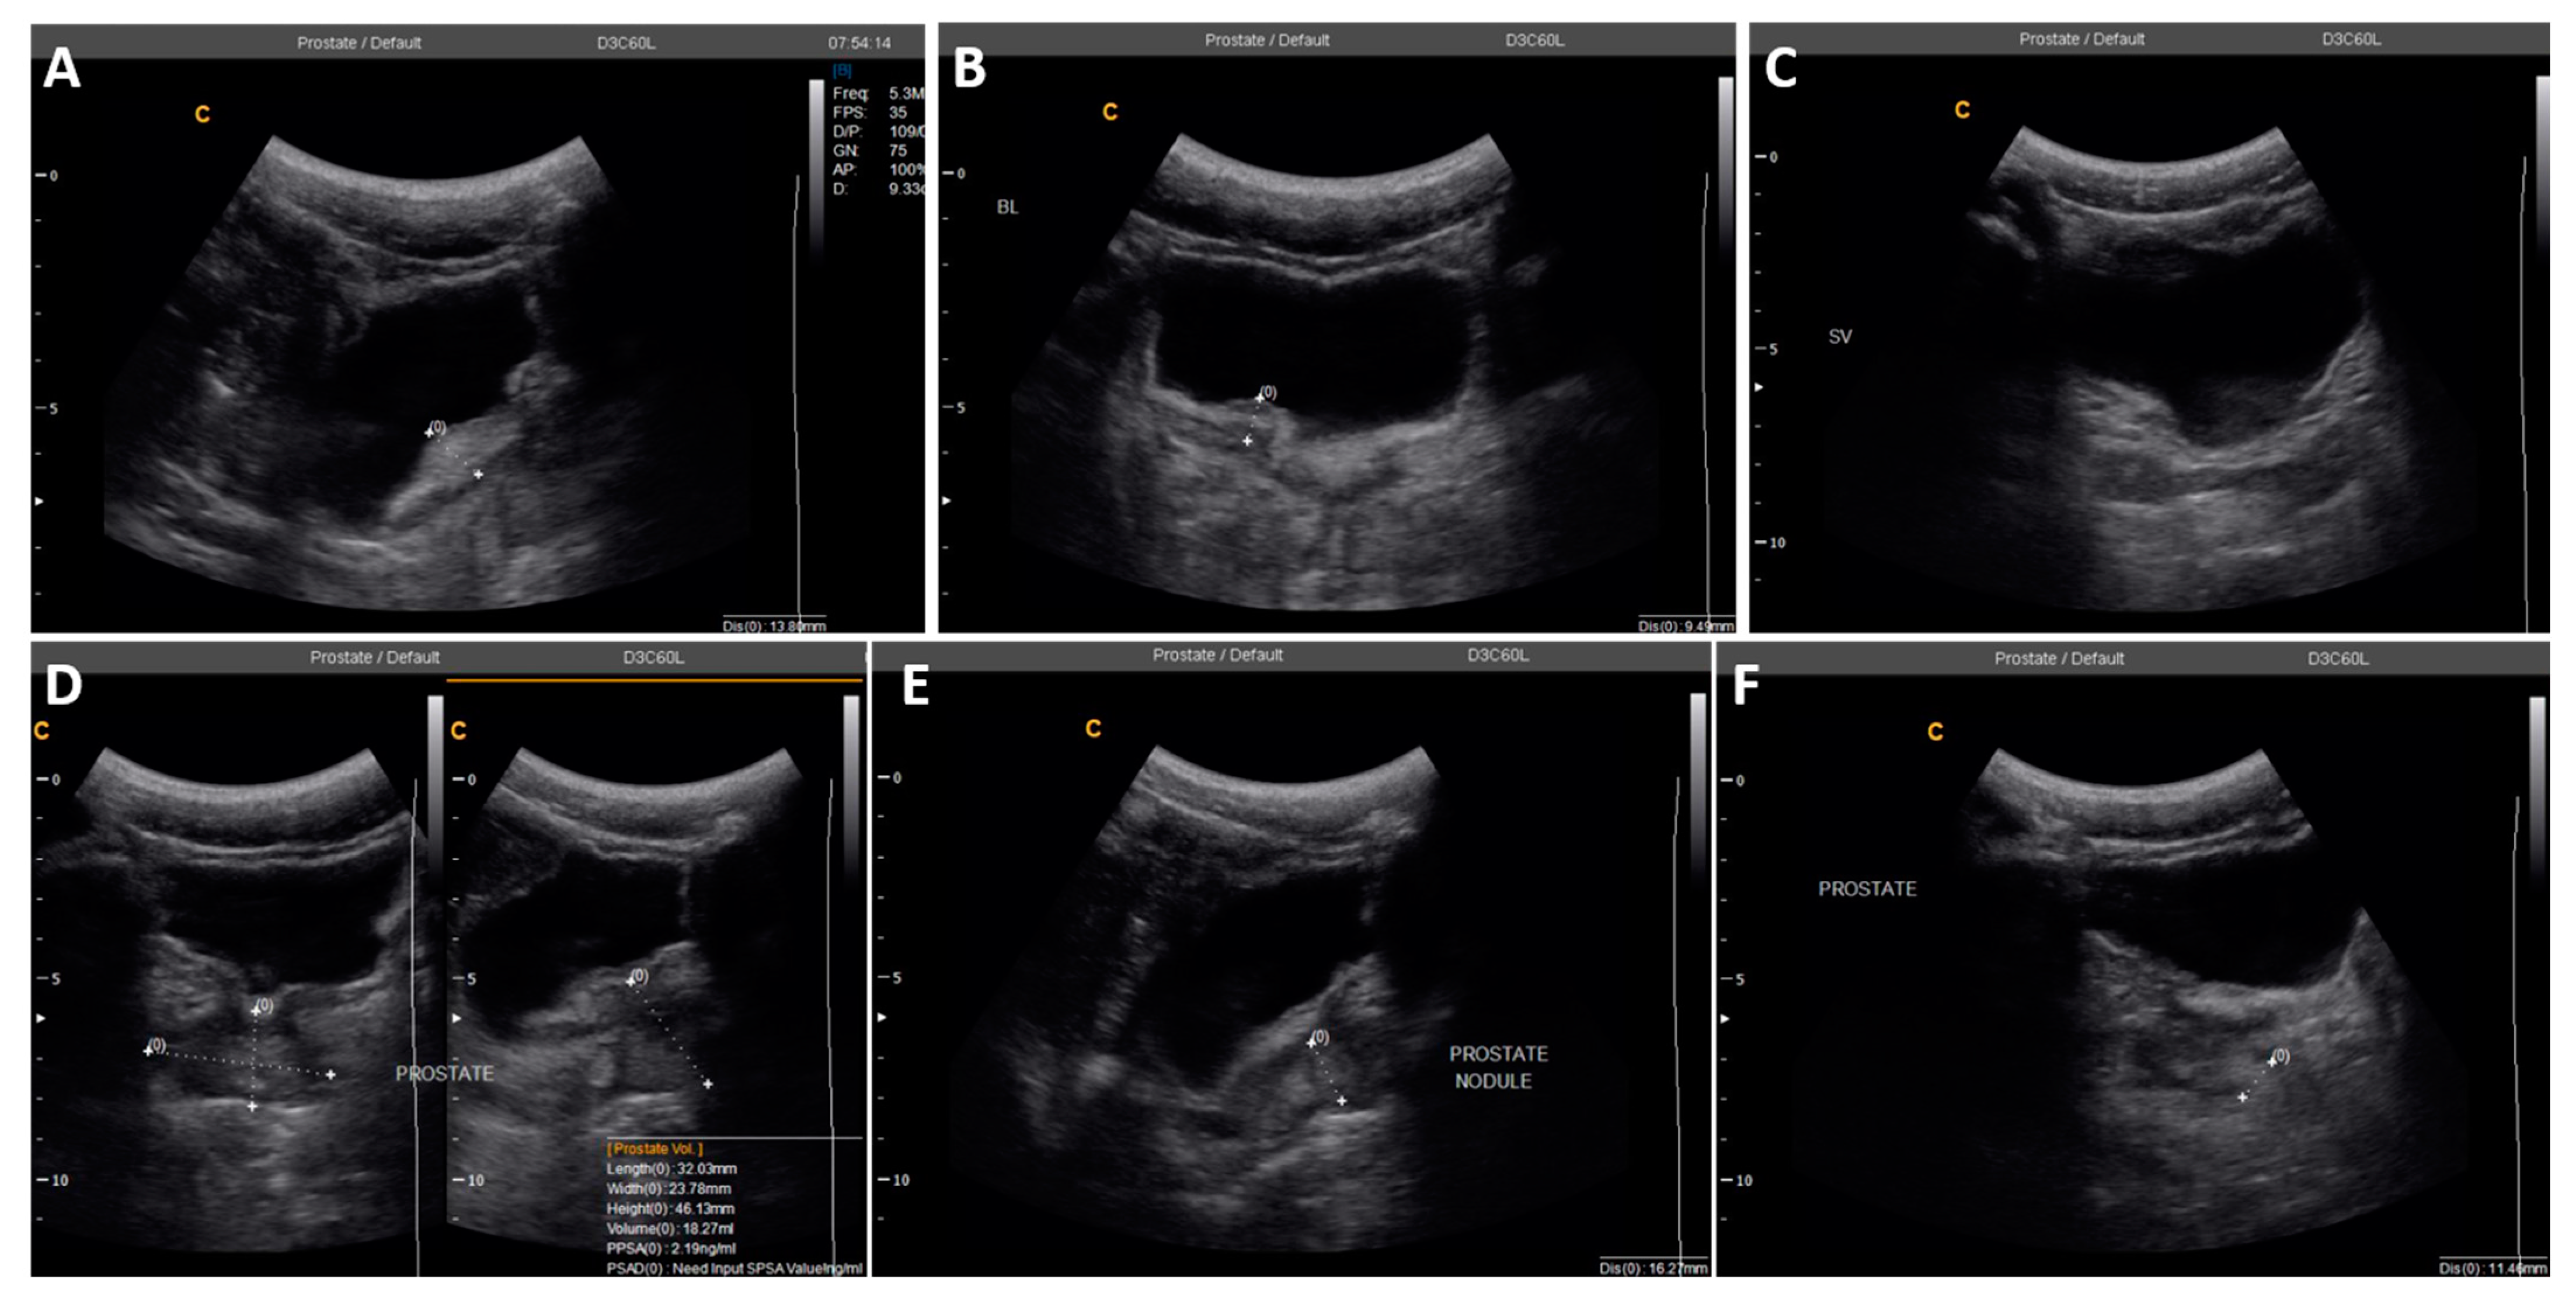

| 2 | 22 | 0 | 0 | 25.4 | Irregular bladder wall with severe focal thickness, irregular prostate with hyperechoic nodule (Figure 3) |

| 3 | 49 | 1 | 6 | N/D # | Left testicular nodule and mild bilateral hydroceles |